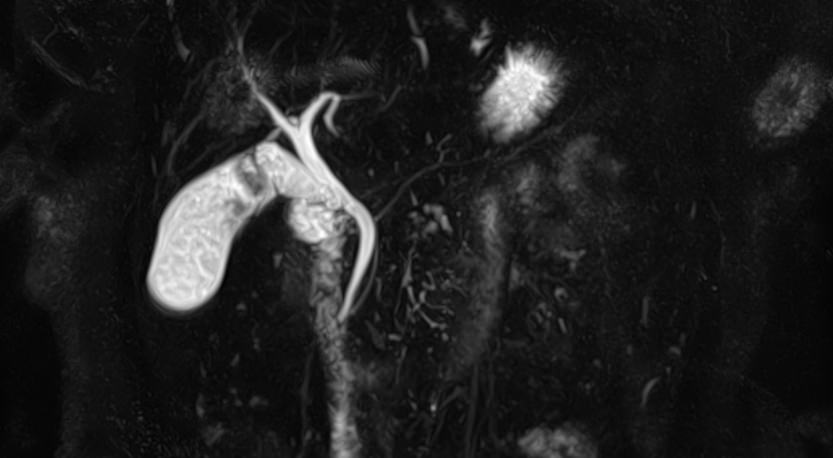

Магнитно-резонансная холангиография – это неинвазивный и безопасный метод исследования, который используется для визуализации желчевыводящих путей, включая внутри- и внепеченочные желчные протоки, панкреатический (Вирсунгов) проток и общий желчный проток (холедох). МРТ позволяет оценить анатомические особенности билиарной системы и определить патологию расположенных рядом структур.

В клинике «Доступная медицина» МР-холангиография выполняется на современном высокопольном томографе закрытого типа TOSHIBA VANTAGE TITAN 1,5 Тесла. Путем послойного сканирования и построения объемных изображений с высокой четкостью и детализацией, аппарат позволяет диагностировать причины возникновения закупорки желчных протоков.

Метод МР-холангиографии имеет высокую информативность и может назначаться перед проведением классической ЭРХПГ (эндоскопической ретроградной холангиопанкреатографии). Преимуществами МР-холангиографии является неинвазивность, отсутствие вредного рентгеновского излучения. Кроме того, исследование не сопряжено с риском развития таких осложнений как острый панкреатит, холангит и др. При этом МР-холангиография имеет важное значение, так как может использоваться как альтернатива ЭРХПГ, если к последней имеются противопоказания, например, аллергические реакции на йодсодержащие контрастные вещества.

- Выявление аномалий развития билиарного тракта.

С помощью магнитно-резонансной холангиографии можно выявить следующие патологии:

- Закупорка протоков конкрементами;

- Доброкачественные и злокачественные опухоли внутри просвета протоков или новообразования, исходящие из окружающих тканей;

- Рубцовые деформации, спайки, стриктуры желчевыводящих путей.

- Аномалии развития желчевыводящей системы.